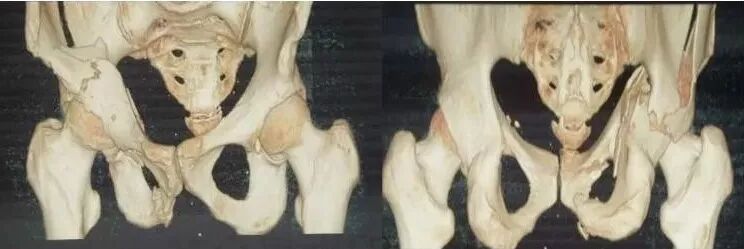

2)骨盆骨折

30min,三个决定:

• 开放性骨折,立即止血;

• 骨盆制动(10-15min);

• 观察10-15min,血流动力不稳定,能否手术?

图片

血流动力学稳定,在7天内手术?

3)髋臼骨折(伤后5-7天)

• 人体最大的负重关节,精确复位可达到关节的最佳匹配,确保正常力学性能;

• 影像学移位程度大,不匹配>2mm--手术;

• 髋关节脱位,髋臼后壁骨折并股骨头骨折,复位后关节仍然不稳,或关节腔有游离骨块--手术。

并发症:异位骨化18-90%;股骨头坏死3-9%